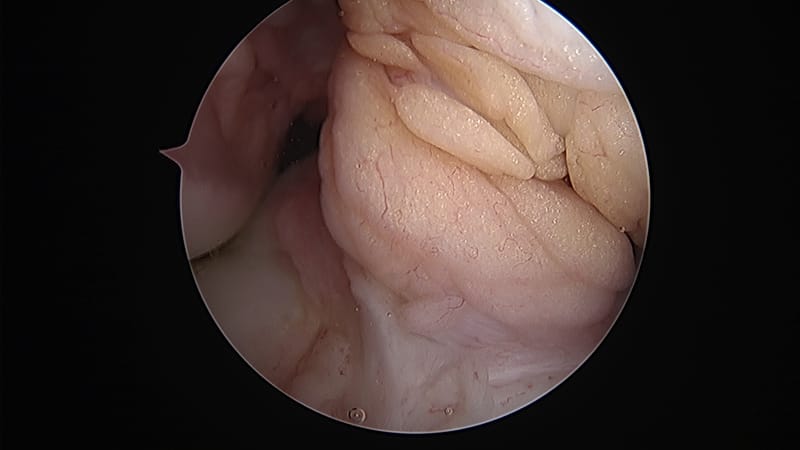

Per i pazienti che presentano una lesione del LCA di grado II o III e che hanno una lacerazione del menisco, esiste un rischio molto più elevato di sviluppo di artrosi in futuro. Per questo motivo di solito si consiglia di eseguire una riparazione, ove possibile, del menisco in associazione ad una ricostruzione del LCA e di eseguire le ricostruzioni del LCA in pazienti giovani o altrimenti attivi e in quasi tutti i pazienti che riferiscono instabilità con attività di torsione o rotazione. La tecnica della chirurgia LCA è cambiata radicalmente negli ultimi anni. Gli innesti di ricostruzione del crociato anteriore eseguiti anni fa erano posizionati più centralmente sia sulla tibia che sul femore - la ricerca ha dimostrato che molti di questi pazienti hanno continui problemi con instabilità di rotazione. Questo problema è stato riconosciuto attraverso un'ampia ricerca clinica e biomeccanica e la tecnica chirurgica è cambiata in cui i tunnel di ricostruzione sono ora posizionati in modo più anatomico per fornire una migliore stabilità al ginocchio, soprattutto per le rotazioni.